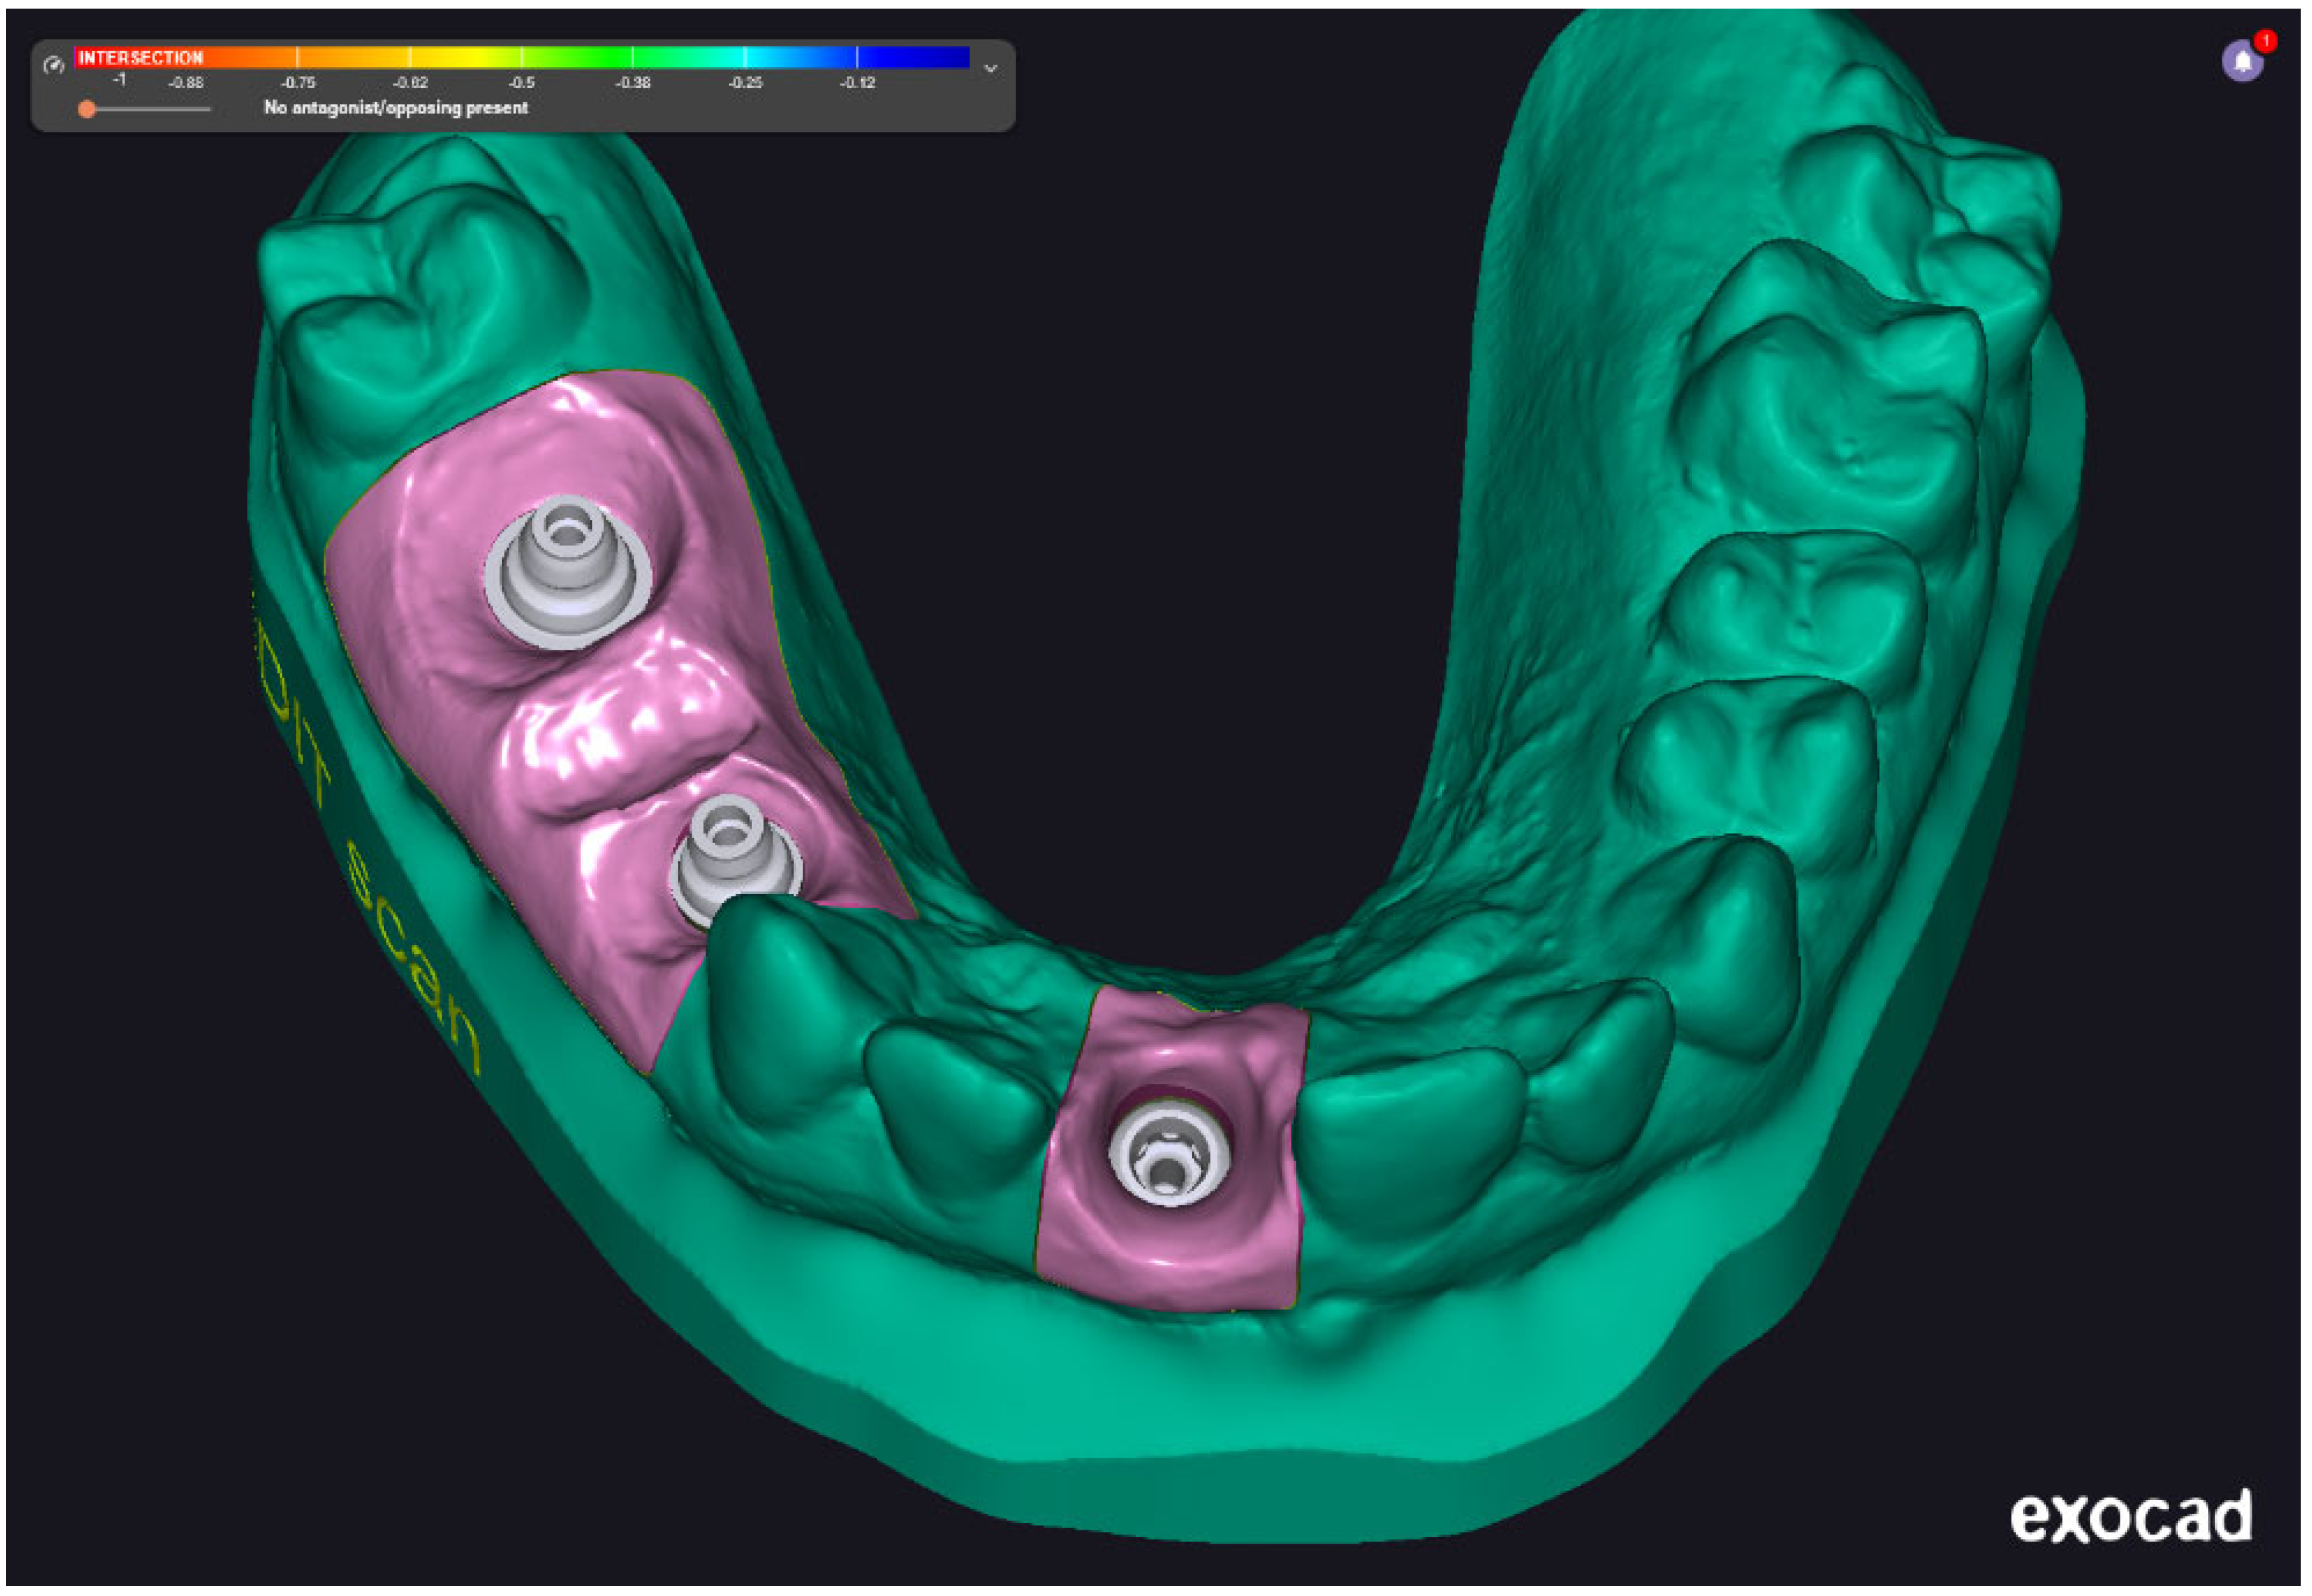

Two intraoral scanners were employed in this study to capture digital impressions: the Medit i700 (Medit Corp., Seoul, Republic of Korea) and the 3Shape TRIOS 3 (3Shape A/S, Copenhagen, Denmark). Both devices offer high-resolution image acquisition and have been validated for use in implant prosthodontics. The digital impression data were saved in STL file format and subsequently processed using Exocad 3.2 Elefsina 9036 DentalCAD software (Exocad GmbH, Darmstadt, Germany). This software facilitated the generation of virtual models, digital framework design, and CAD/CAM workflow integration. Final models and restorations were fabricated via additive and subtractive manufacturing using high-resolution 3D printing and milling systems. Two examples were presented in Figure 3. The examples are not from our cases; it is just illustrative, to present the digital impressions.

Figure 4 shows a finalized digital model made with the help of an impression acquired using Medit i700 intraoral scanner. The scan captures three implant scan bodies and surrounding soft tissue contours within the mandibular arch. The color-coded gingiva mask (highlighted in pink) represents the digitally defined emergence profile and anatomical boundaries of the peri-implant region. This digital model serves as the foundation for virtual prosthetic design and framework planning, enabling precise evaluation of implant angulation, spatial constraints, and occlusal integration prior to CAD/CAM fabrication.

The scan data captured with the TRIOS 3 system enabled accurate reproduction of soft tissue contours and implant emergence profiles, supporting precise prosthetic adaptation. The model demonstrates high anatomical fidelity and is used for laboratory fit verification of the digitally designed restoration (Figure 5a). In Figure 5b, the model features a three-unit implant-supported fixed partial denture on a soft tissue analog base. The gingiva mask and restoration were fabricated based on scan data captured with the Medit scanner. The resulting model offers comparable anatomical accuracy and restorative detail, validating the Medit system’s suitability for clinical and laboratory digital workflows.

Figure 4. Exocad screenshots with the digital model prepared with the impression acquired with Medit intraoral scanner.

Prosthesis 07 00135 g004

Figure 5. (a)—Restoration and 3D-printed dental model generated from a TRIOS 3 intraoral scan. (b)—Restoration and 3D-printed dental model generated from a Medit i700 intraoral scan.

Prosthesis 07 00135 g005